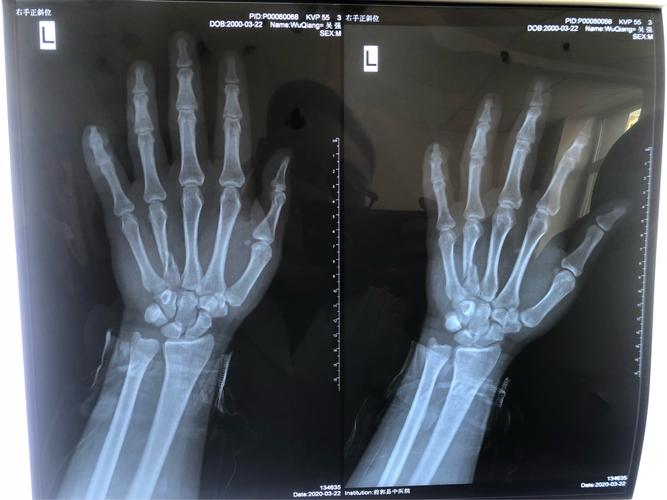

门诊dr片:左手小指末节指骨部分缺如,左手第四掌骨螺旋形骨折,断端